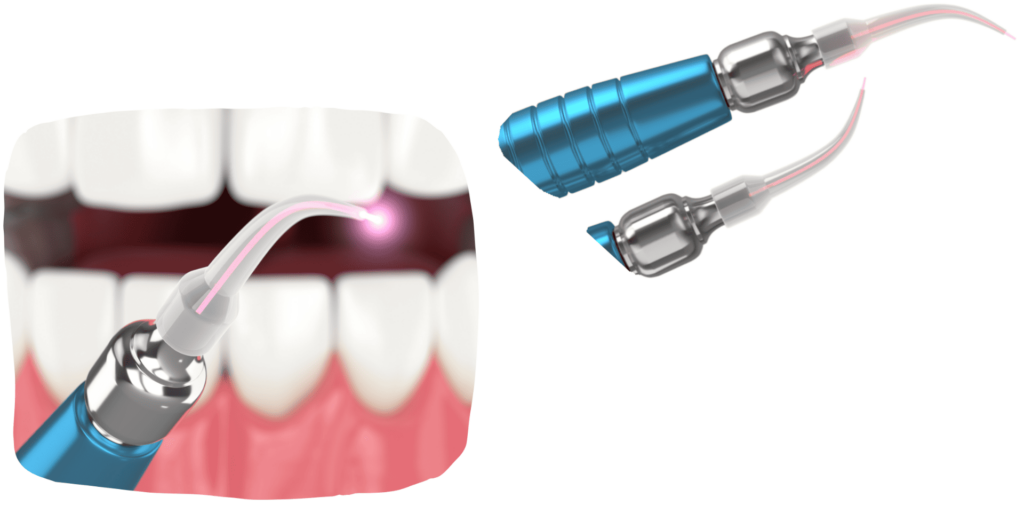

DENTAL LASER

The use of laser in oral surgery achieves exceptional results, as it enables precise tissue treatment with minimal damage to surrounding structures, significantly reduces post-operative pain and swelling, accelerates healing and tissue regeneration, and reduces the risk of infection thanks to its antibacterial effect.

The dental laser significantly improves the safety and success of oral surgical procedures.